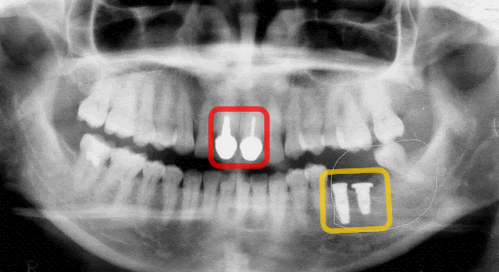

ご参考までに、私の歯の写真も見てみましょう。

2本の前歯のはっきりした白いものは、セラミック人工歯です。

向かって右側の奥歯2本が倒れるようにあるのがよくわかります。

ちなみに、これを抜いて現在、吉本歯科医院にてインプラント治療中です(^^)。

歯が骨から抜けたままにしておくと、このように手前に倒れてきます。

そうなると噛むことができなくなり左と右など全体のかみ合わせのバランスが崩れてきます。

恐がりの私は数年ほっといていたため左ではほとんど噛めていませんでした(反省(>_<))

というわけで、今回これではダメだ!どんどん崩れると思いインプラント治療をしました。

向かって右下に見える白いのがインプラントです。

手術から約数ヶ月今はなにもせずただただインプラントが自分の骨とくっつくのを待つだけです。(*^_^*)